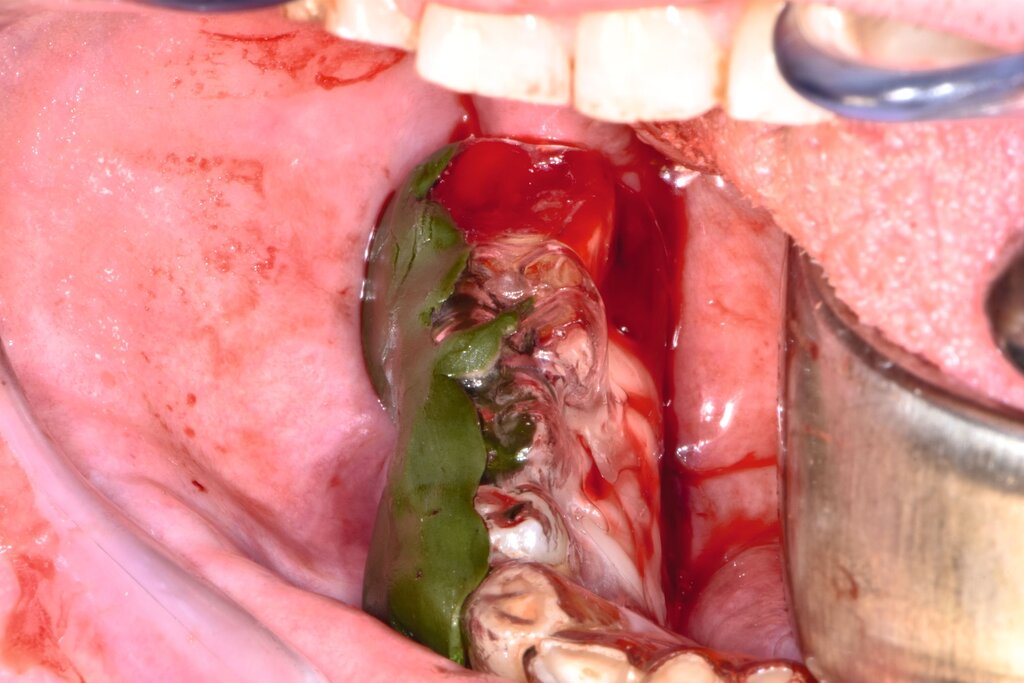

Der Patient stellte sich mit freiliegendem Knochen in Regio 43 bis 47 und mehreren gelockerten Zähnen vor. 45 und 46 waren devital. Als klinische Besonderheit fiel auf, dass sich innerhalb der Nekrosezone kleinflächige Weichgewebsareale darstellten, die in dieser Form bei klassischen Osteonekrosen üblicherweise nicht beobachtet werden. Eine klassische Vincent-Symptomatik bestand nicht. Drei Wochen zuvor war eine Herpes-Zoster-Infektion dermatologisch diagnostiziert und zunächst stationär behandelt worden. Der Patient erhielt eine intravenöse, antivirale Therapie, die bei Entlassung oralisiert wurde.

Therapeutisch erfolgte eine gezielte Sequestrotomie und nur zwei Zahnentfernungen. Auf eine plastische Deckung wurde bewusst verzichtet. Stattdessen wurde Platelet-Rich Fibrin (PRF) auf die Wundfläche appliziert und mit einer Verbandplatte geschützt. Unter vorübergehender enteraler Ernährung über eine Magensonde zeigte sich eine nahezu vollständige Schleimhautregeneration innerhalb weniger Wochen. Eine kleine Restläsion in Regio 44 lingual heilte unter lokaler Therapie mit Chlorhexidin und einer Occlusivpaste vollständig ab. Eine Kontrollszintigrafie nach sechs Monaten bestätigte die weitgehende Ausheilung.

Im beschriebenen Fall wurde nach der Sequestrotomie, die eine ausgedehnte Knochenwundfläche hinterließ, ergänzend PRF appliziert, um die Weichgewebsheilung zu fördern und zugleich auf eine plastische Deckung verzichten zu können. Der Einsatz von PRF bot dabei eine biologische Unterstützung der sekundären Schleimhautheilung und ermöglichte eine nahezu komplikationslose Wundregeneration trotz der großflächigen Exposition. Klinische Studien belegen eine beschleunigte epitheliale Regeneration und eine geringere Inzidenz von Wunddehiszenzen nach PRF-Anwendung [Temmerman, 2016]. Ein solcher Heilungsverlauf wäre bei Medikamenten-assoziierten oder Strahlen-bedingten Osteonekrosen in der Regel nicht zu erwarten, da dort (unter anderem) eine persistierende Gefäßschädigung und eine chronische Ischämie bestehen. Im Gegensatz dazu ist die Durchblutung bei der Herpes-Zoster-assoziierten Osteonekrose nach Abklingen der akuten Vaskulitis meist wiederhergestellt, was eine weitgehend physiologische Regeneration des Gewebes ermöglicht.